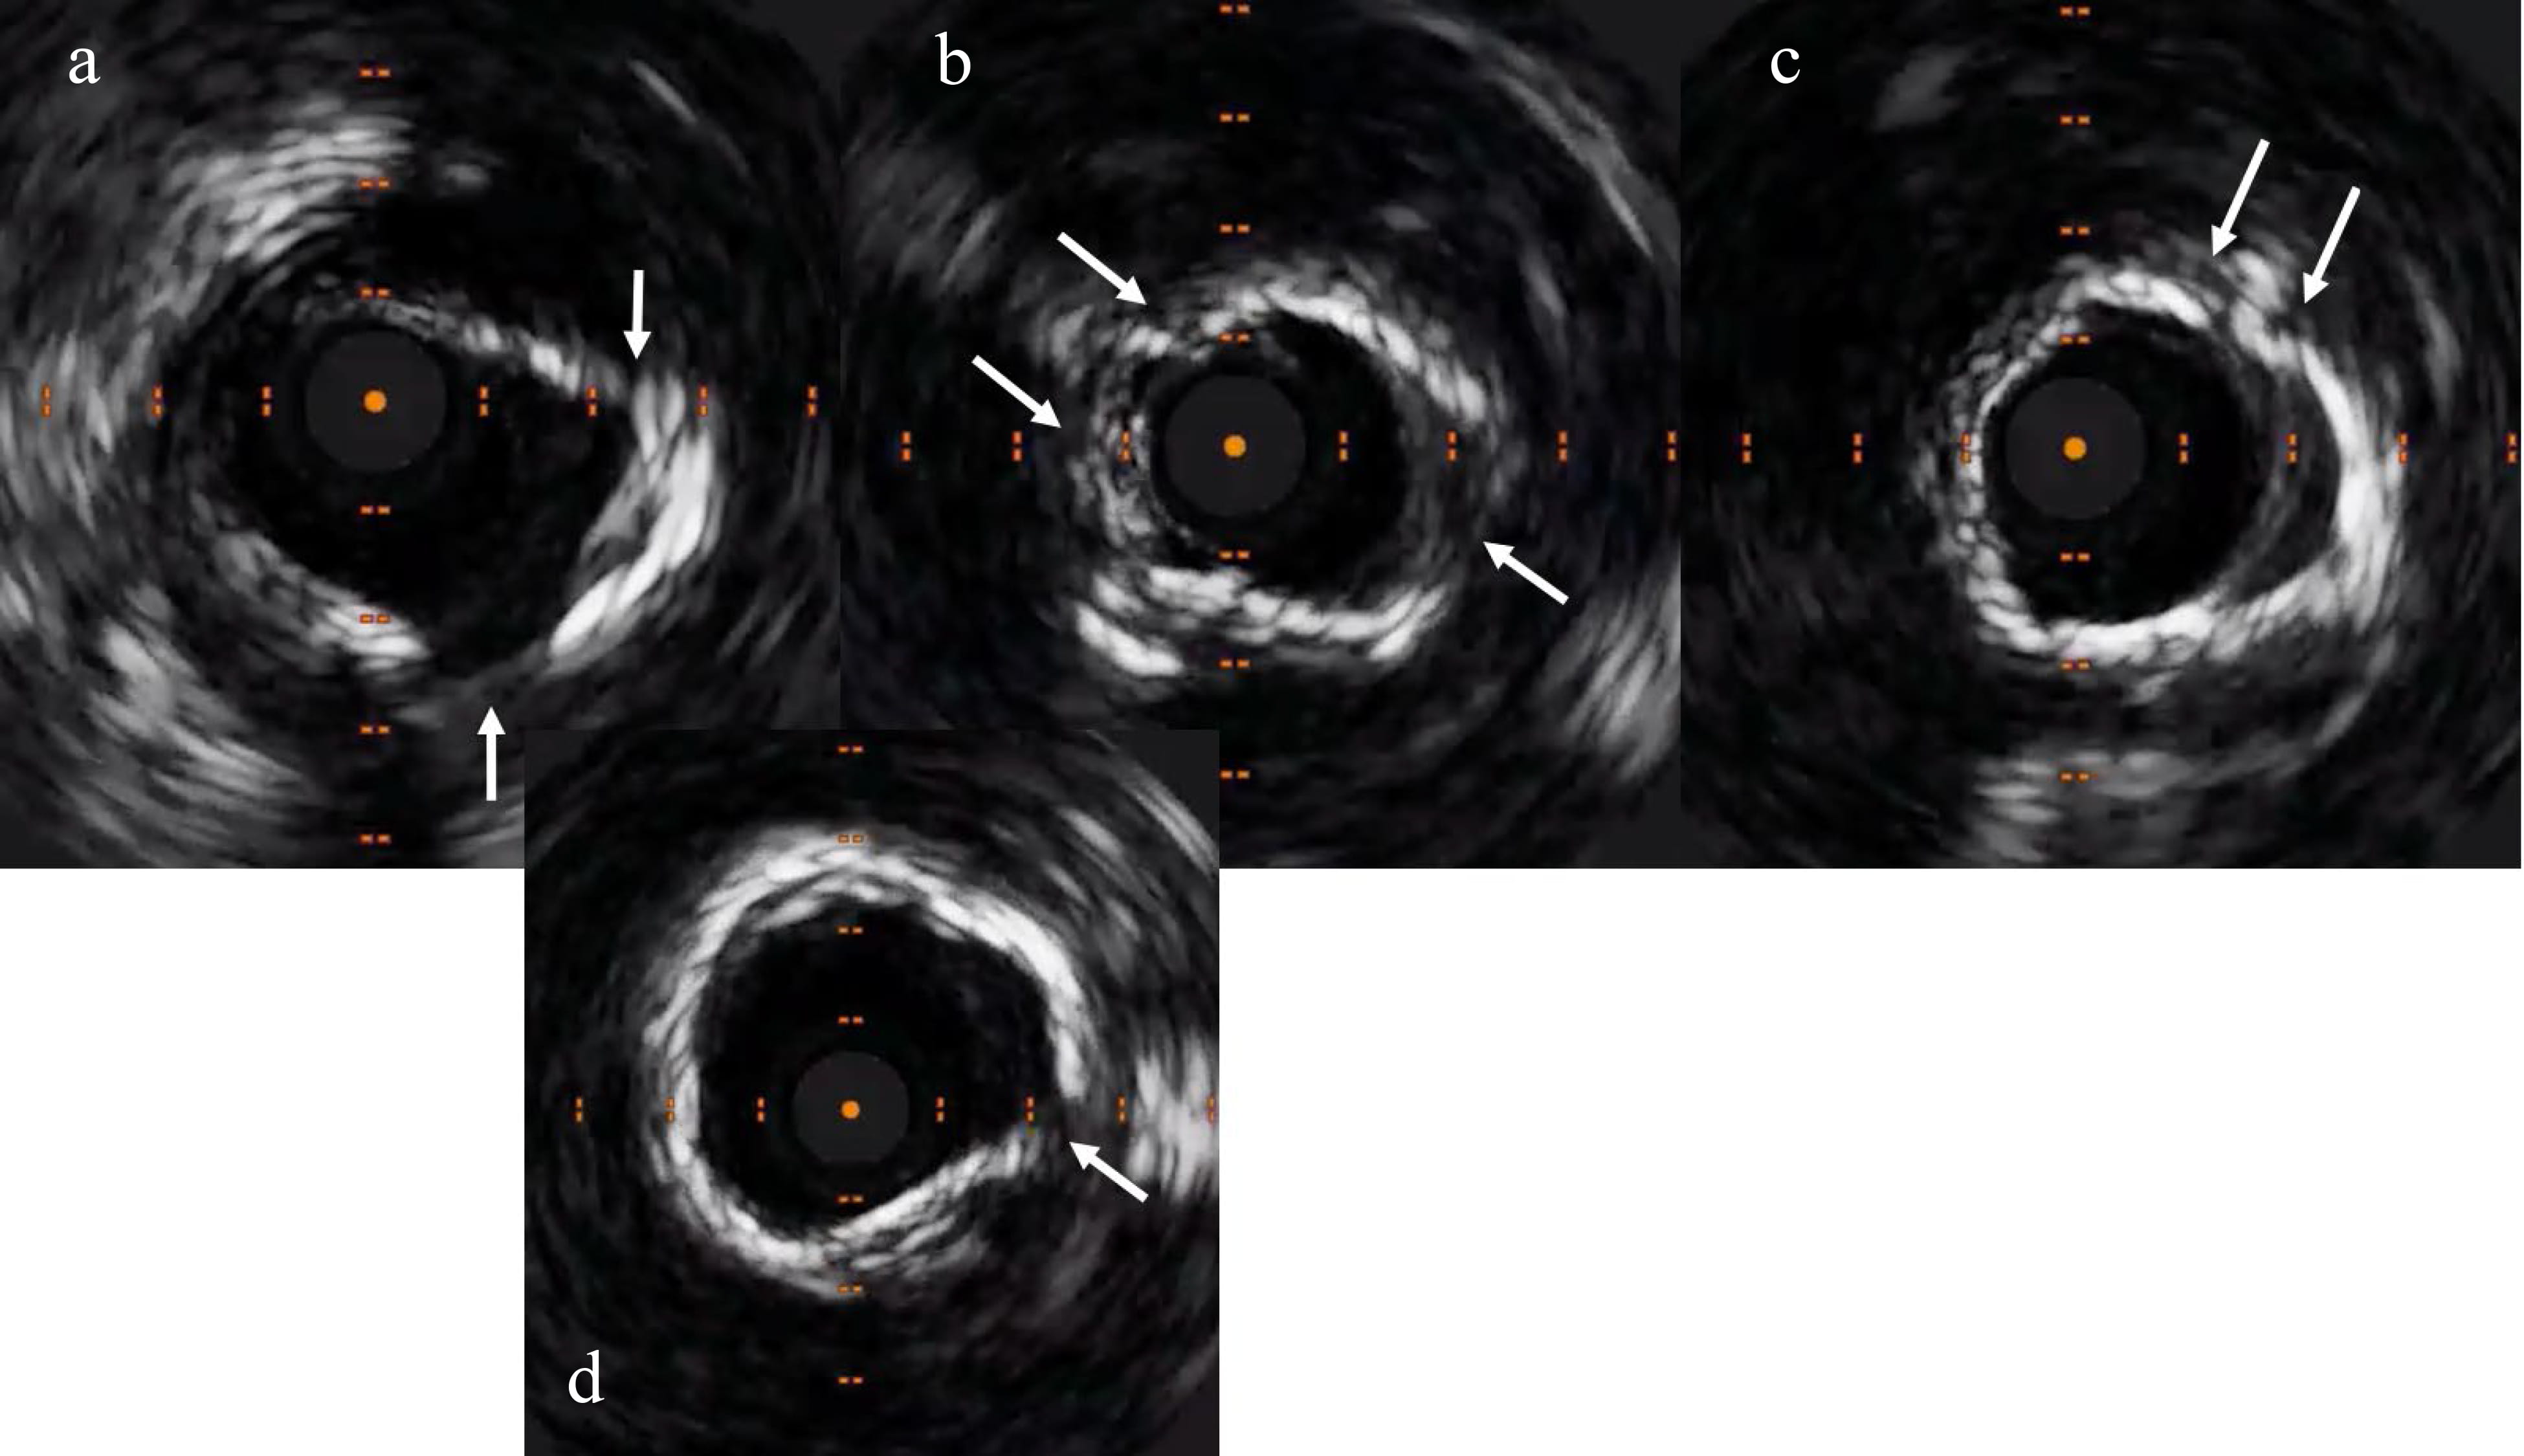

intra-vascular lithotripsy (IVL) balloon (Fig. 5), which fractured the calcium

which was confirmed on repeat intra-vascular imaging (Fig. 6). A long DCB (3.5

Fig. 5.Repeat IVUS exhibiting crack in the calcium (shown by the arrows). (a) Cracks at 2 and 5’o clock positions. (b) Cracks at 4 and 10’o clock positions. (c) Crack at 1’o clock position. (d) Crack at 3’o clock position (shown by the arrows).